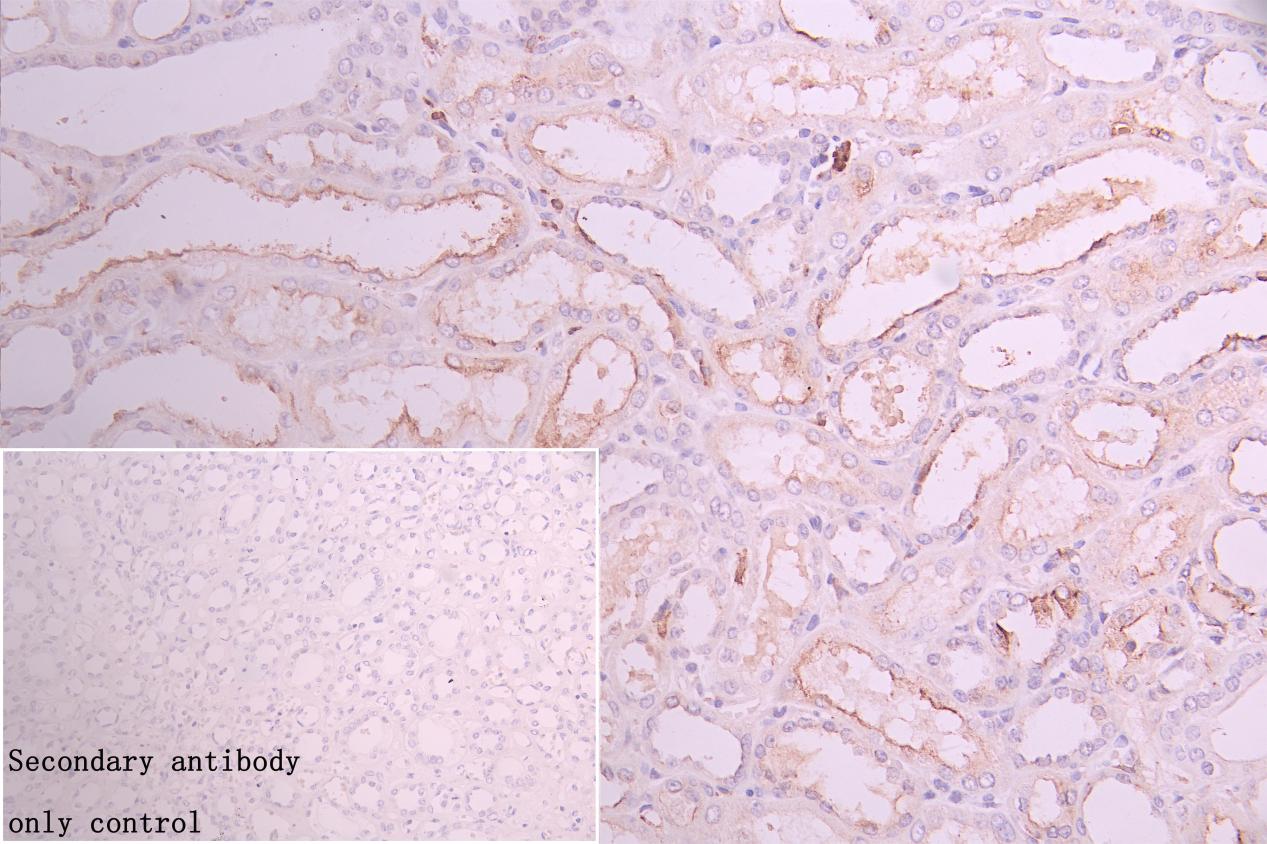

IHC image of CSB-RA974628A0HU diluted at 1:50 and staining in paraffin-embedded human kidney tissue performed on a Leica BondTM system. After dewaxing and hydration, antigen retrieval was mediated by high pressure in a citrate buffer (pH 6.0). Section was blocked with 10% normal goat serum 30min at RT. Then primary antibody (1% BSA) was incubated at 4°C overnight. The primary is detected by a Goat anti-rabbit polymer IgG labeled by HRP and visualized using 0.05% DAB. Secondary antibody only control: uses 1% BSA instead of primary antibody